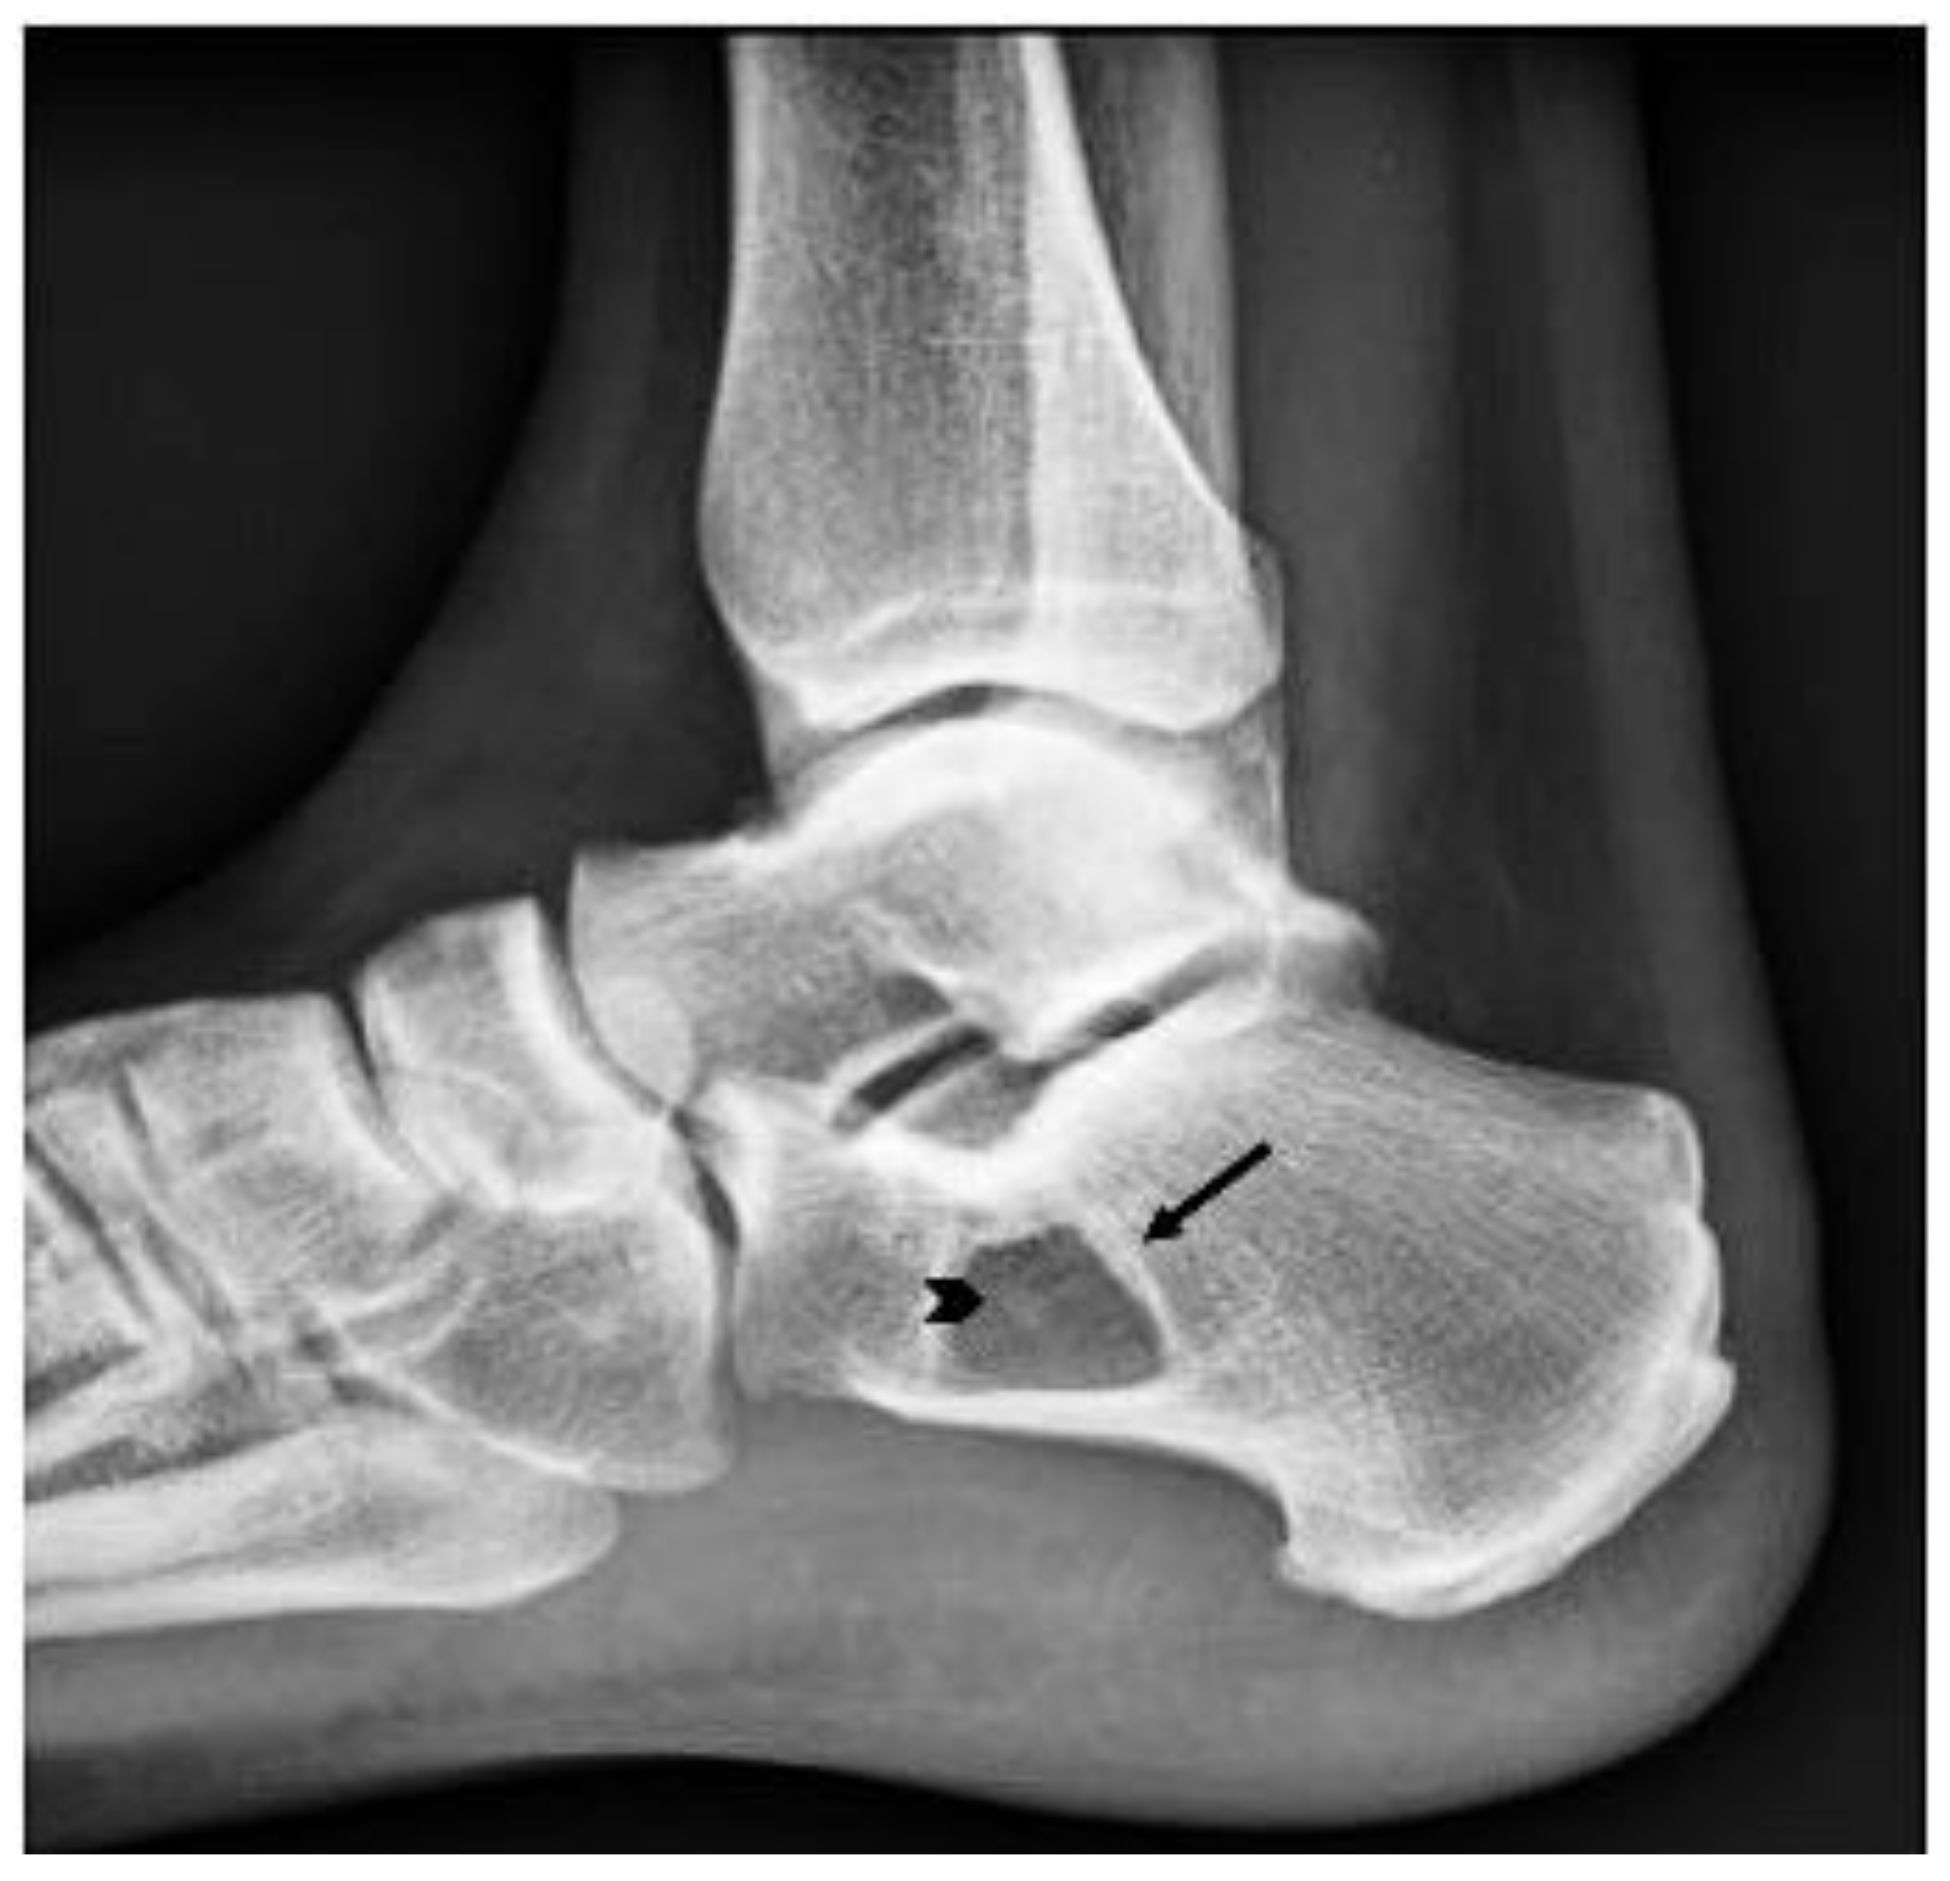

2. Case Presentation